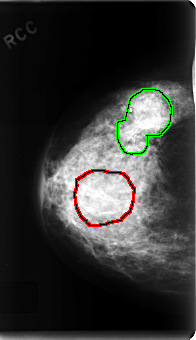

C_0223_1.RIGHT_CC

FILE: C_0223_1.RIGHT_CC.OVERLAY

TOTAL_ABNORMALITIES 2

ABNORMALITY 1

LESION_TYPE MASS SHAPE OVAL MARGINS OBSCURED

ASSESSMENT 3

SUBTLETY 4

PATHOLOGY BENIGN

TOTAL_OUTLINES 1

BOUNDARY

ABNORMALITY 2

LESION_TYPE CALCIFICATION TYPE PLEOMORPHIC DISTRIBUTION CLUSTERED

LESION_TYPE MASS SHAPE OVAL MARGINS ILL_DEFINED

ASSESSMENT 5

SUBTLETY 5

PATHOLOGY MALIGNANT